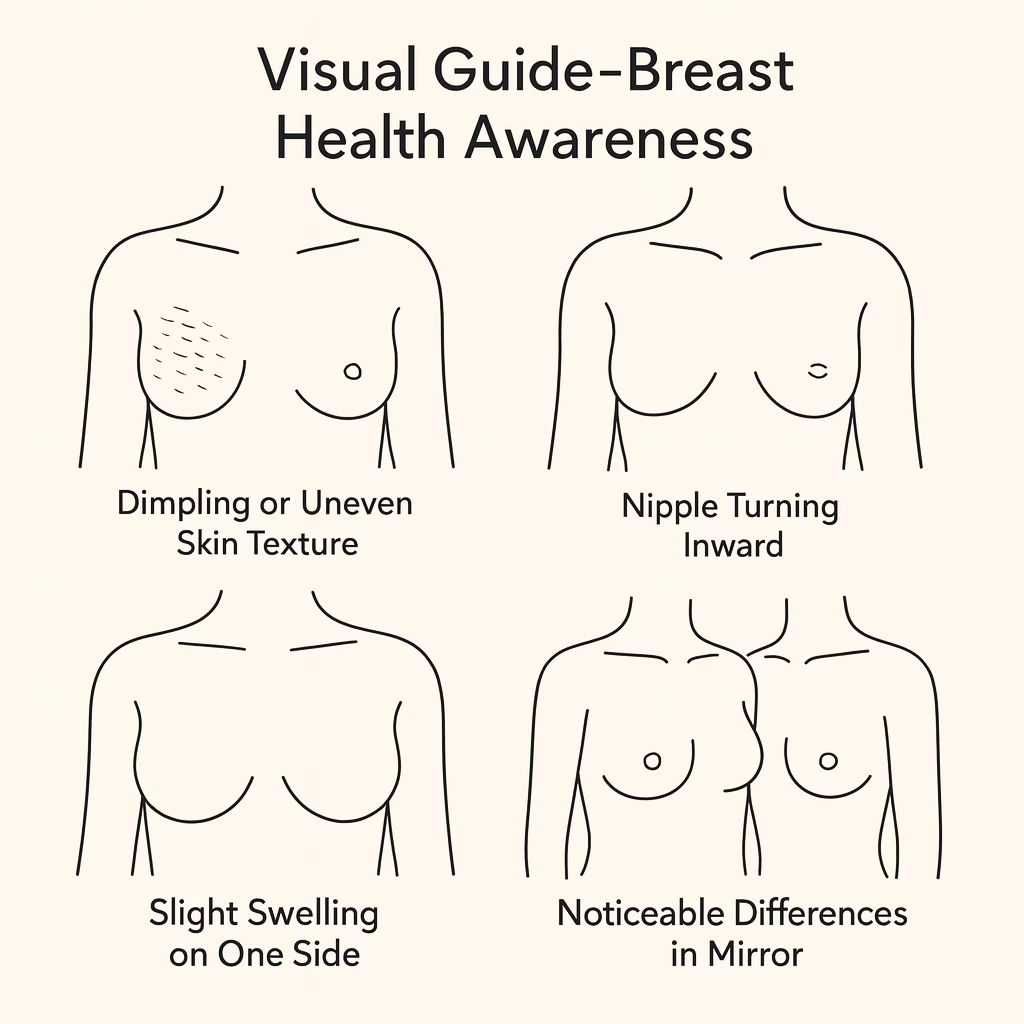

Visual Guide – Breast Health Awareness Illustrations

Illustrations are helpful tools for learning about breast health. They show how early changes might look without creating fear or confusion. Since real medical images may feel uncomfortable for some people, educational illustrations provide a clearer and more comfortable way to understand common signs.

Illustrations may show examples such as:

- Dimpling or uneven skin texture

• Nipple turning inward

• Slight swelling on one side

• Noticeable differences when comparing both breasts in the mirror

These illustrations are only for general guidance. They cannot confirm what a specific symptom means because every body is different. If any visual change makes you feel unsure, a medical consultation is the best step.